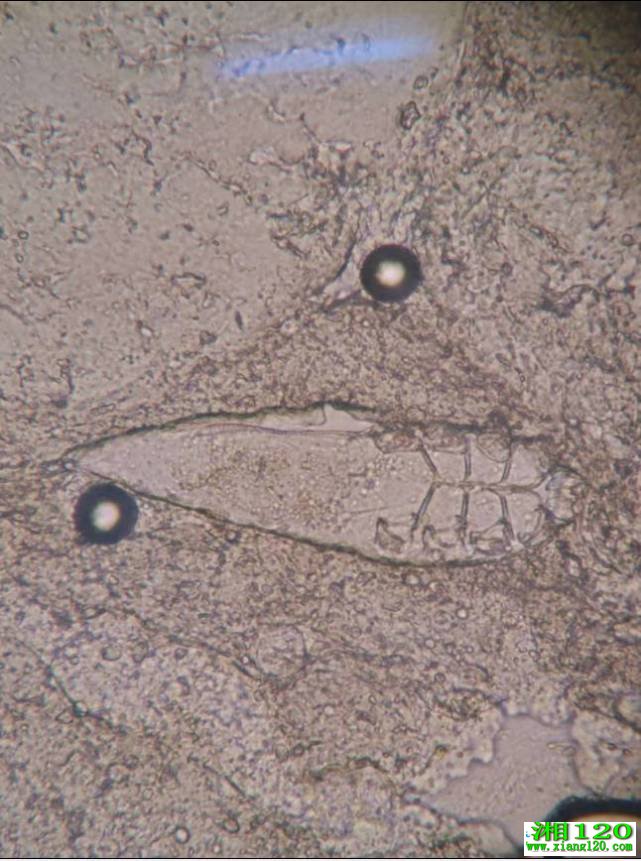

徐东医生从患者眼睛上取下3根睫毛,放在显微镜下观察。果然,其中一根睫毛上面有3只螨虫在缓慢蠕动。一般认为,3根睫毛中1根有超过三只螨虫,即可确诊为螨虫引起的前部睑缘炎。

▲显微镜下的蠕形螨